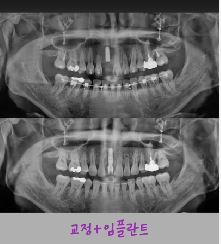

제목 교정중 임플란트는 언제 심을까요?

* 교정 중, 임플란트는 언제 심을까요?  *

교정 중 임플란트 타이밍은 결과를 좌우하는 중요한 포인트입니다.

✔ 대부분은 교정이 어느 정도 진행된 후

→ 공간 정리 & 치아 위치가 안정된 뒤 식립

✔ 경우에 따라 교정 중 식립도 가능

→ 교정용 기준점(앵커) 역할로 활용하기도 함

✔ 무조건 먼저 심는 건 위험

→ 치아 이동 계획이 바뀌면

임플란트 위치 수정  불가